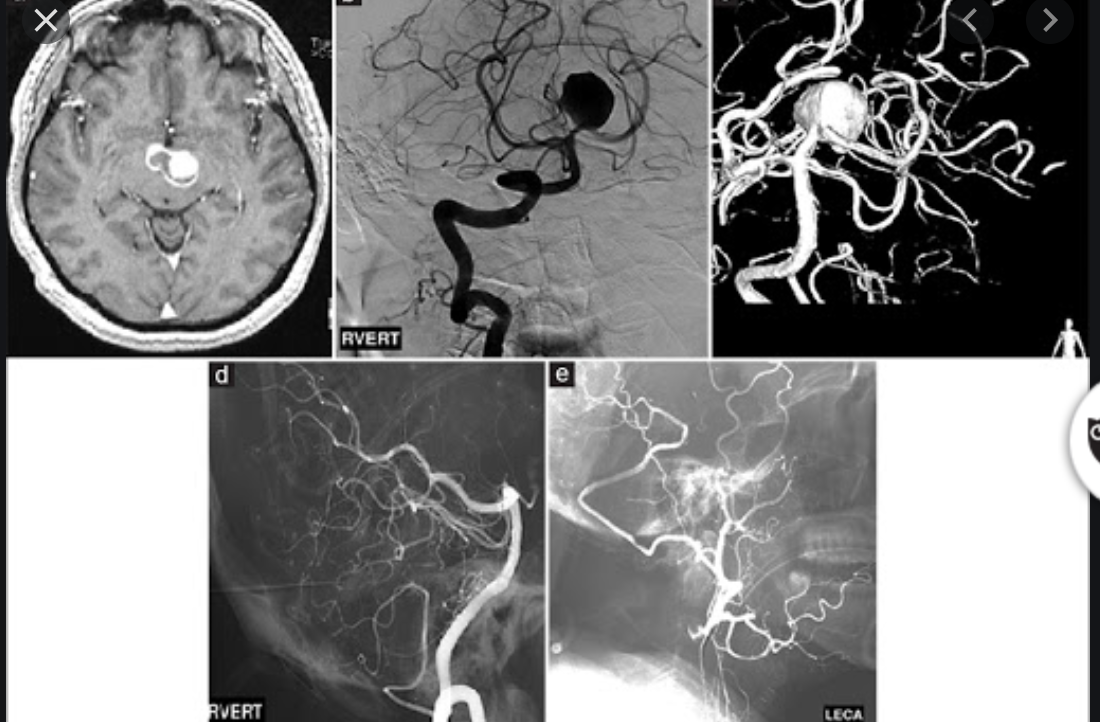

Angiography

Angiography remains the gold standard in full characterisation of the lesion. It enables to individually catheterise feeding vessels. Morphologically a spherical or ellipsoid varix may be visualised. Venous drainage is via the median prosencephalic vein (MPV), the straight sinus (if present) and then out via the transverse/sigmoid sinuses. By definition, there should be no drainage to other components of the deep venous system 6.

Radiographic features

CT

may present as a lobulated hyperattenuating structure anterior to the mid brain

rupture of a basilar artery aneurysm is typically localised to the interpeduncular cistern, but may extend into the suprasellar cistern

CT angiography (CTA) provides better evaluation of the aneurysm and its relationship to other branches of the basilar artery

basilar artery aneurysms can be both fusiform and saccular 2

better than CTA for evaluating the relationship of the basilar aneurysm with branch vessels off the basilar artery, which is critical when considering intervention